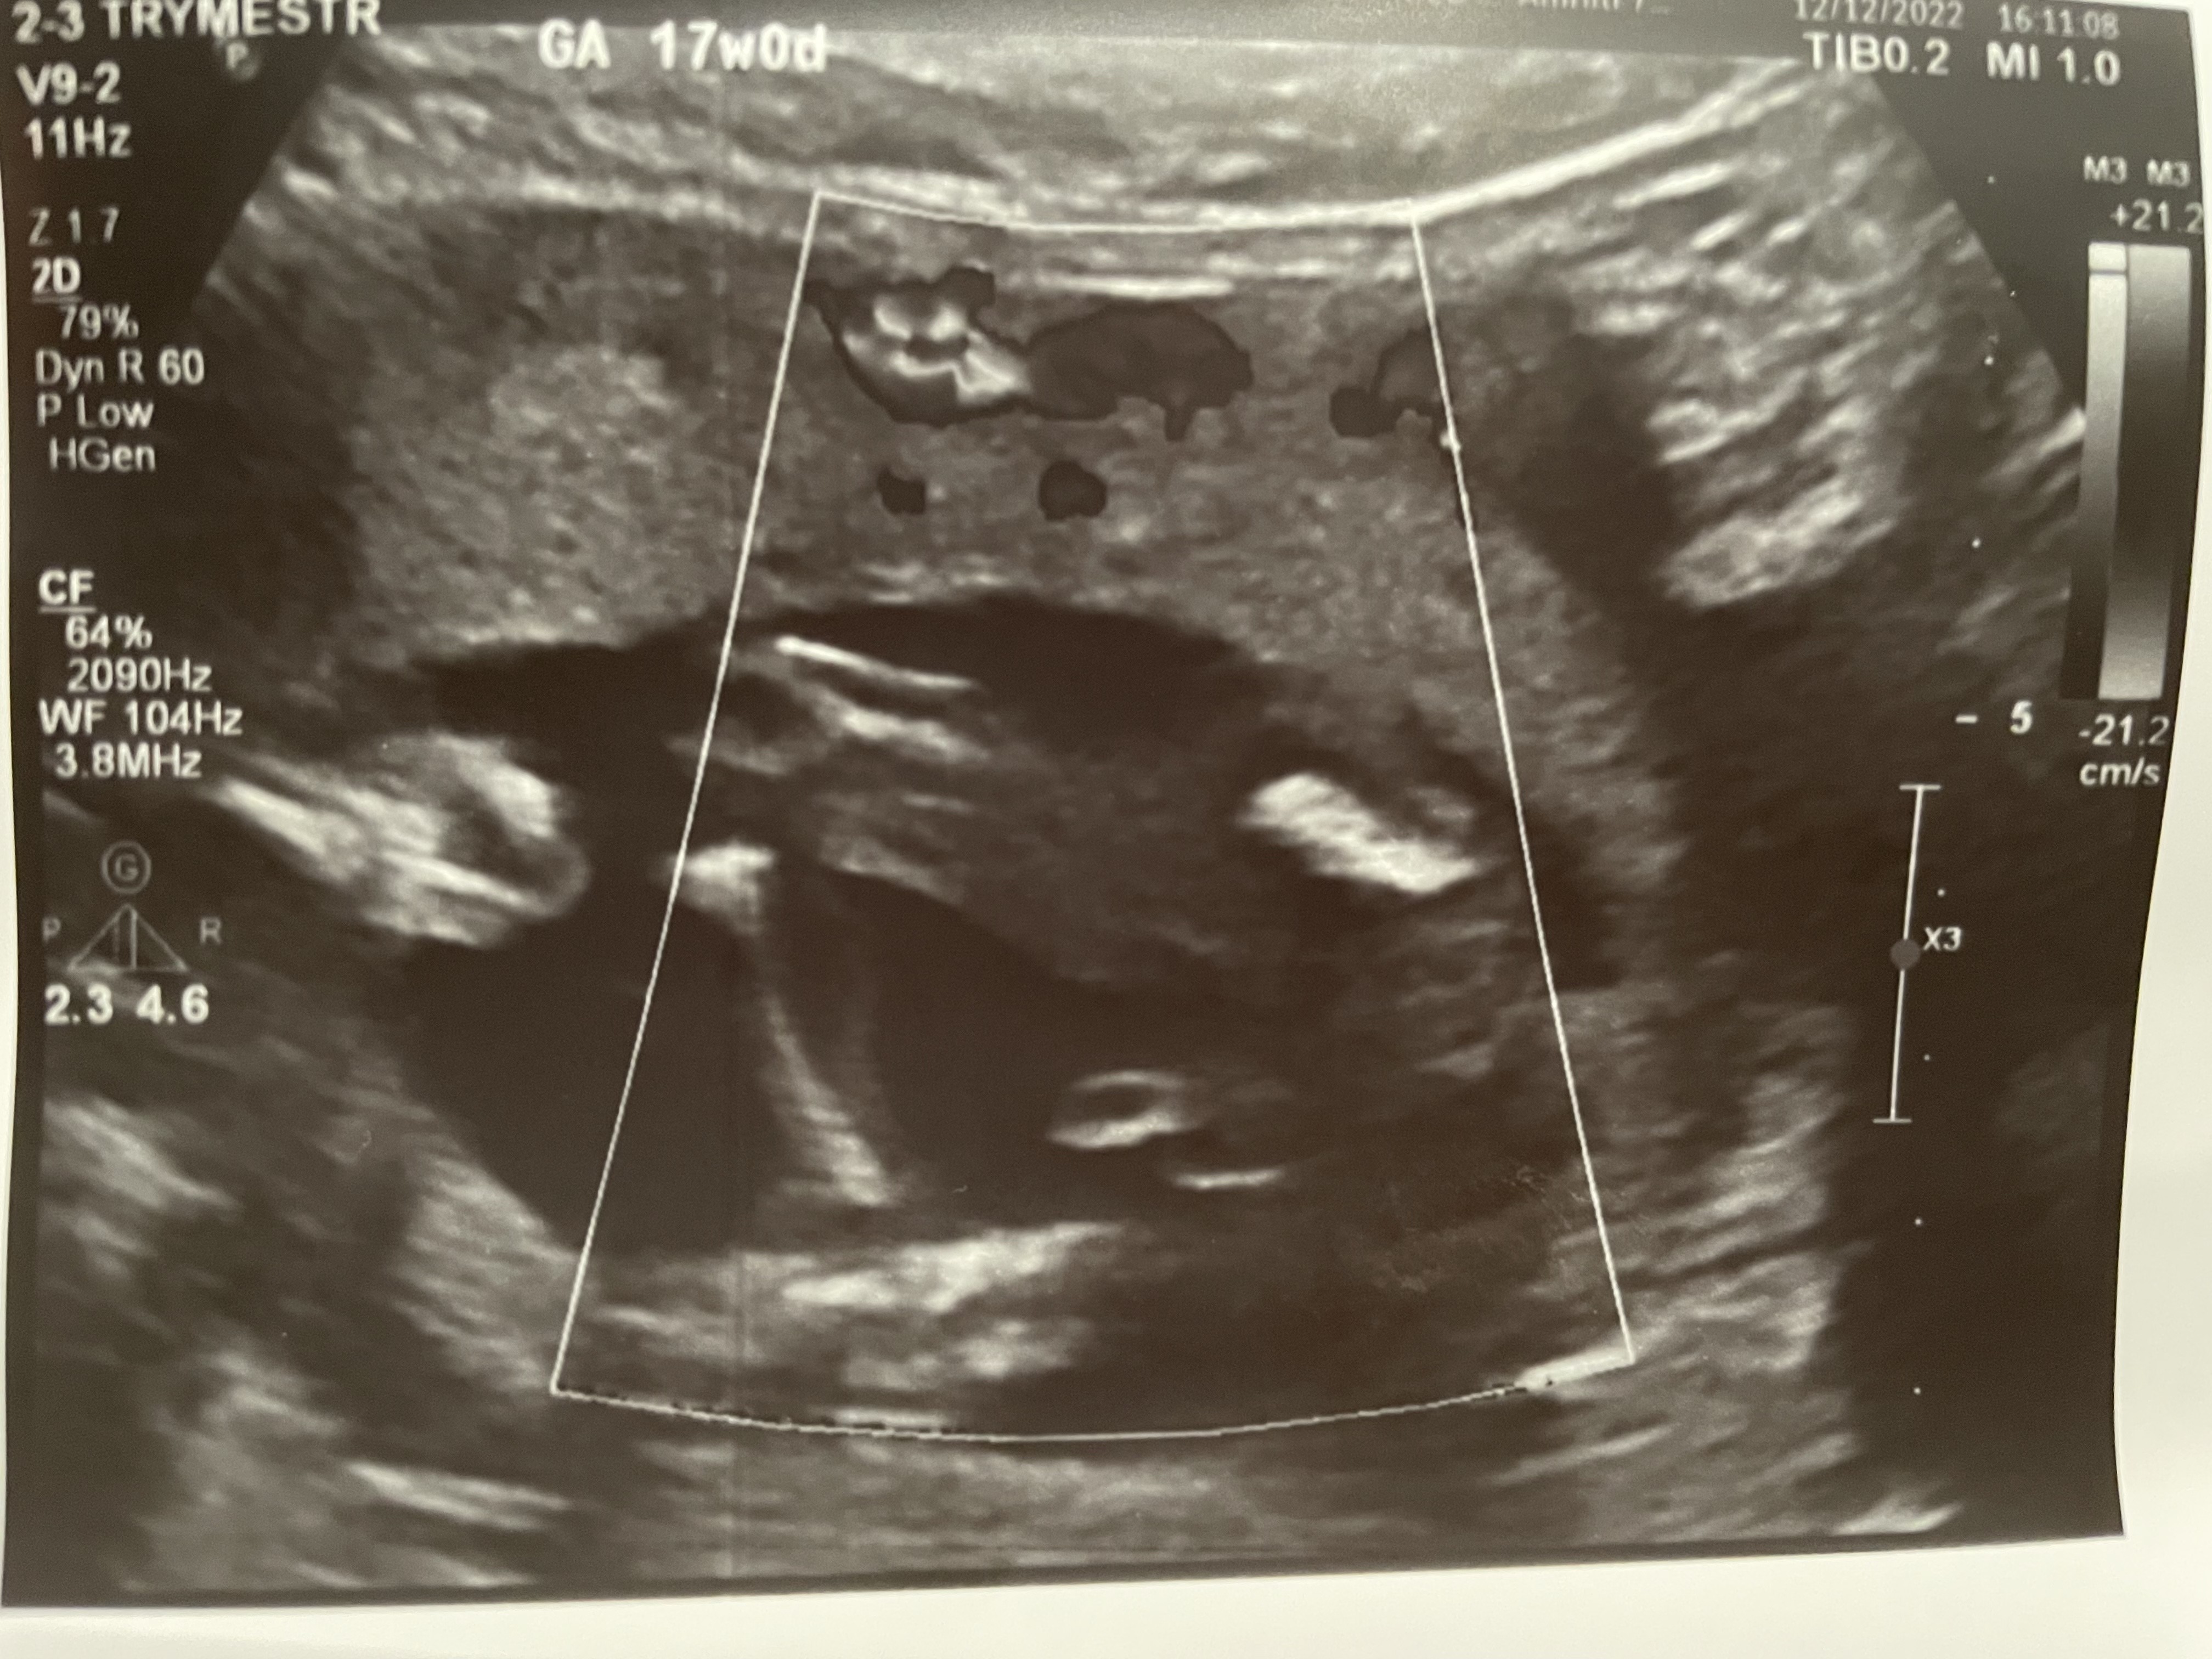

Wczoraj miałam wykonane USG, na którym moja prowadząca Pani ginekolog oceniła, że na monitorze widzi chłopca. Nie powiem, poczułam lekki zawód, ciągle się z tym oswajam. Ale mam pytanie do Was. Czy zdarzyło się której z Was, że na badaniach połówkowych okazało się jednak, że zamiast chłopca jest dziewczynka? Słyszałam o takich przypadkach, ale nigdy nie poznałam osobiście nikogo komu by się to przytrafiło.

Dołączę zdjęcie z USG, na którym ponoć widać siusiaka.